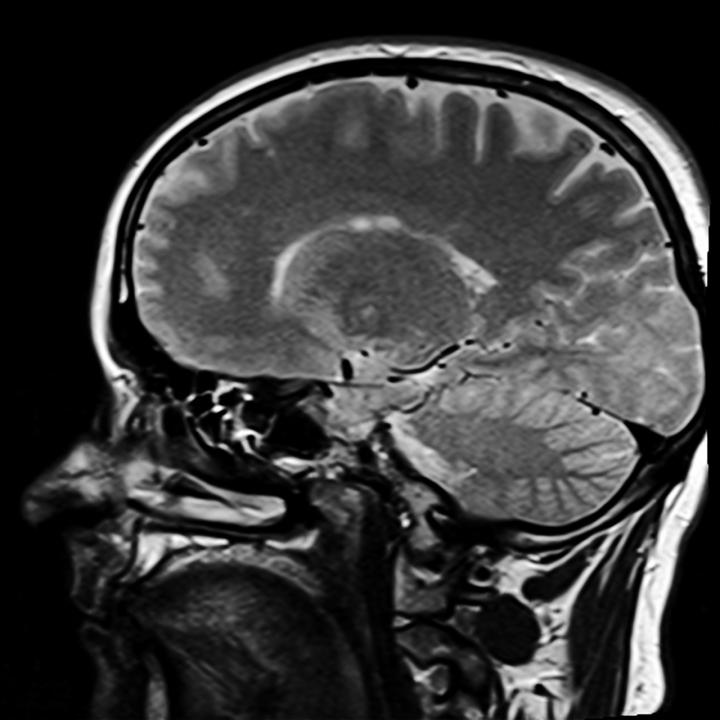

Scientists at The University of Manchester have shown for the first time that if the brain is 'tuned-in' to a particular frequency, pain can be alleviated.

Nerve cells on the surface of the brain are co-ordinated with each other at a particular frequency depending on the state of the brain. Alpha waves which are tuned at 9-12 cycles per second have been recently associated with enabling parts of the brain concerned with higher control to influence other parts of the brain.

For instance researchers at the Human Pain Research Group at The University of Manchester found that alpha waves from the front of the brain, the forebrain, are associated with placebo analgesia and may be influencing how other parts of the brain process pain.

This led to the idea that if we can 'tune' the brain to express more alpha waves, perhaps we can reduce pain experienced by people with certain conditions.